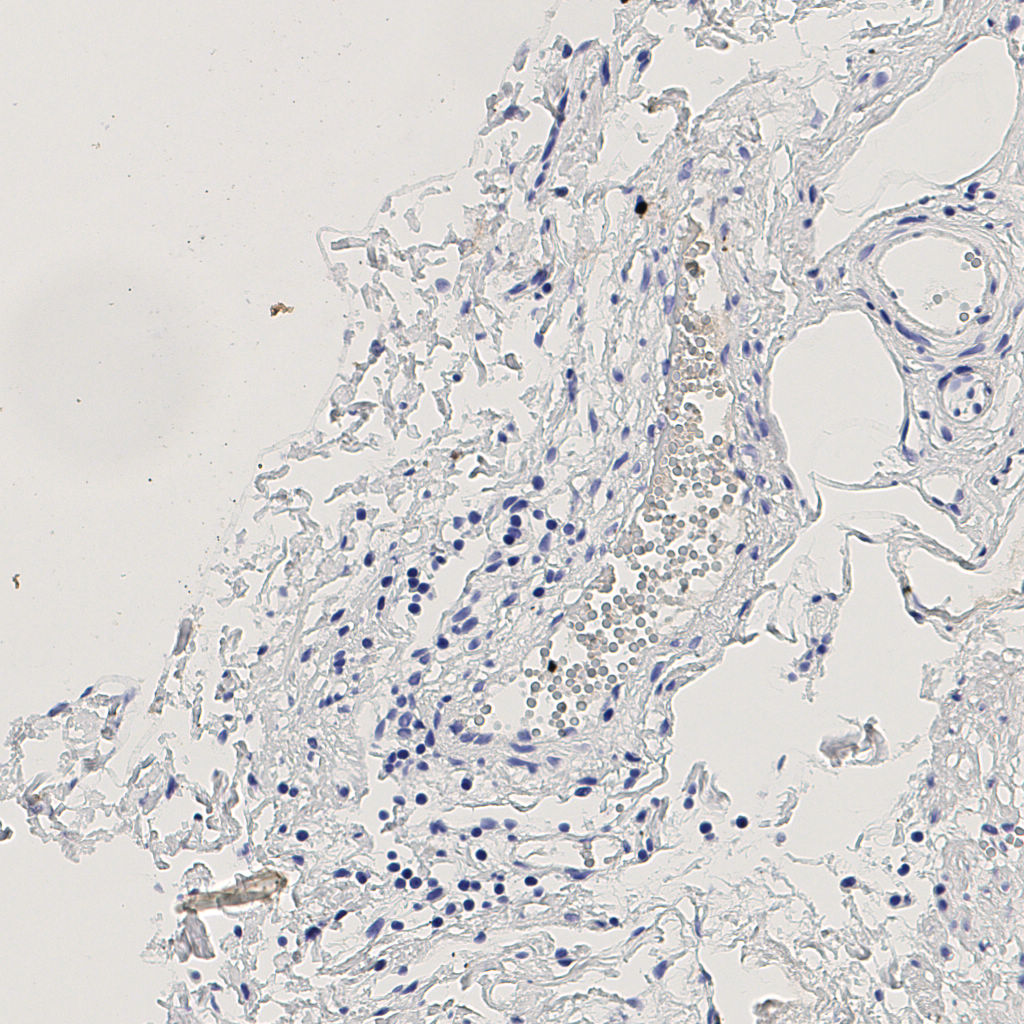

7.85%

Ki67 指数

阴 1104 阳 94